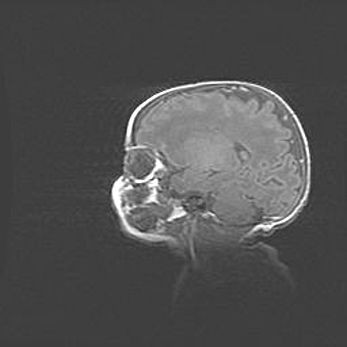

Церебральная ишемия II.

Возраст: 5 дней

Вес: 3400 г

Пол: женский

Окружность головы: 35 см

Срок гестации: 39 недель

Церебральная ишемия – это заболевание, характеризующееся недостаточностью (гипоксией) либо полным прекращением (аноксией) снабжения мозга кислородом по причине закупорки одного или нескольких сосудов. Это приводит к  что метаболическим расстройствам различной степени тяжести в тканях головного мозга, развитию коагуляционных некрозов и гибели нейронов.